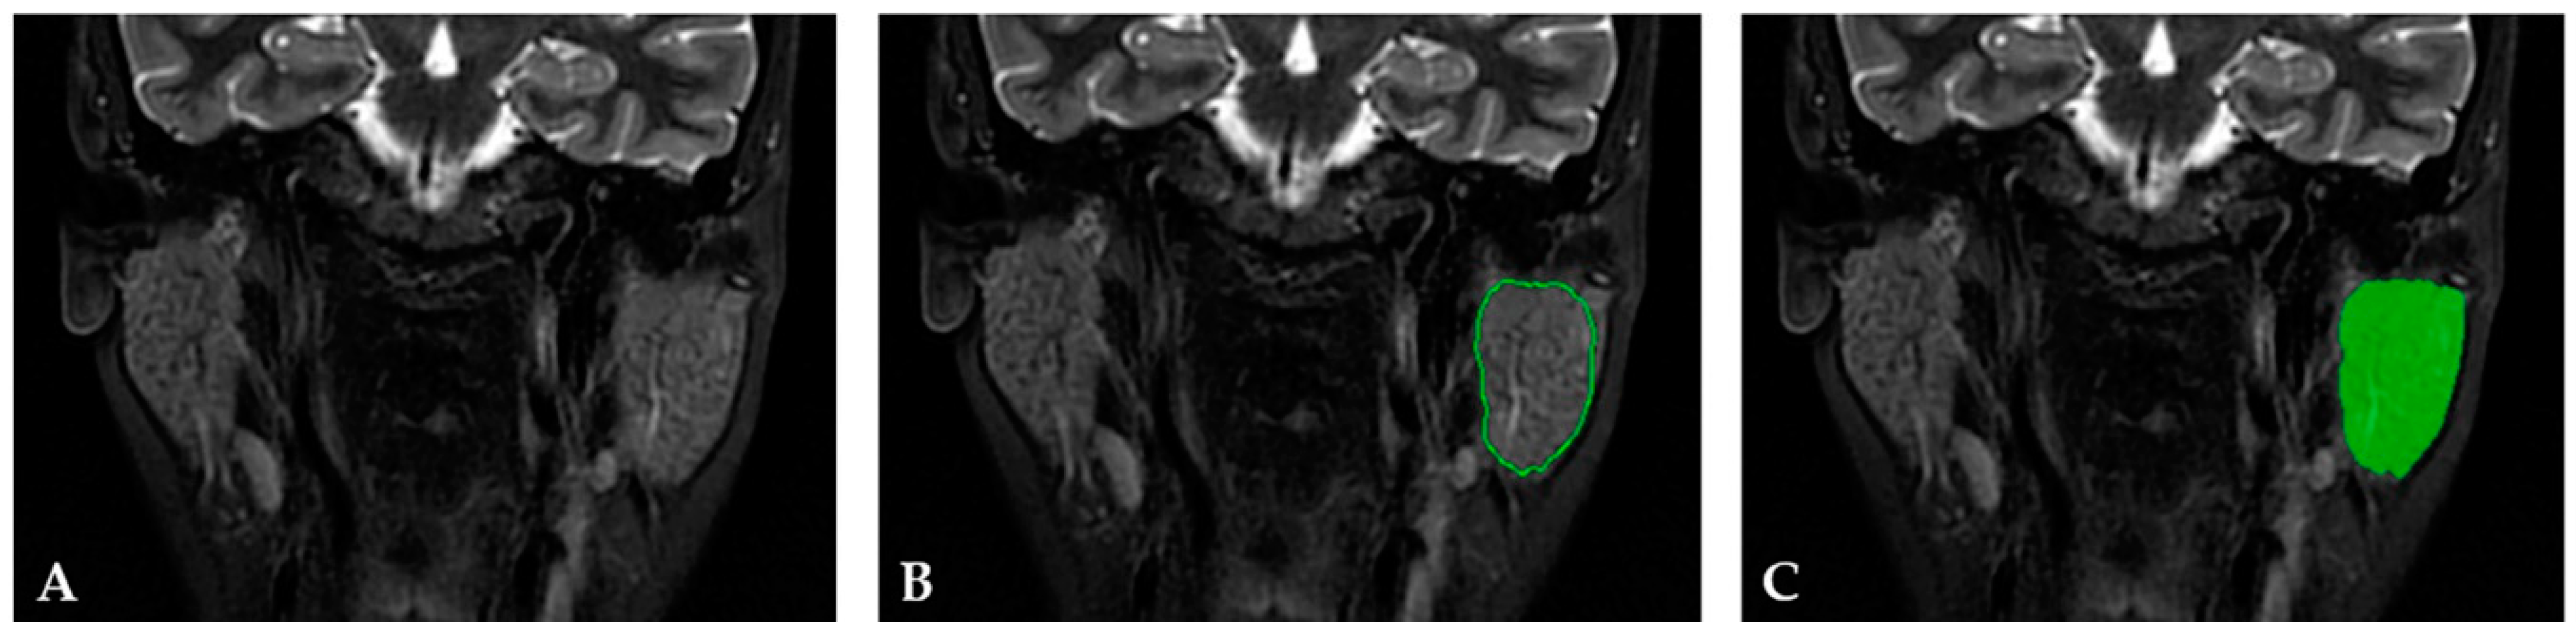

2.3.1. Image Preprocessing and Segmentation